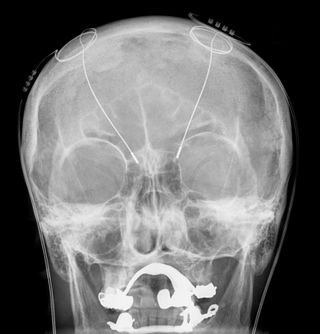

التحفيز العميق للدماغ Deep brain stimulation (DBS)، هو علاج جراحي بإدخال جهاز طبي يسمى منظم الدماغ والذي يرسل نبضات كهربائية إلى مناطق محددة من الدماغ. اختيار التحفيز العميق لمناطق معينة من الدماغ يوفر فوائد علاجئية سواء لحالات المقاومة للعلاج أو للاضطرابات العاطفية مثل الألم المزمن، مرض پاركنسون، الرعاش والديستونيا.[1] بالرغم من التاريخ الطويل للتحفيز العميق للدماغ،[2] فإن المبادئ والآليات الأساسية له لا تزال غامضة.

يقوم العلاج بالتحفيز العميق للدماغ على إيصال موجات كهرومغناطيسية إلى مناطق عميقة في الدماغ. ويجري التحفيز عبر وضع أسلاك كهربائية في مناطق معيّنة على الرأس كي تنطلق منها موجات كهرومغناطيسية لتصل إلى مراكز في وسط منتصف الدماغ، يُعتَقَد بعلاقتها مع الإدراك والعواطف والمزاج. ولحد الآن، نجحت هذه الطريقة في علاج أمراض نفسية تتضمّن الكآبة.[3] ولذا رأت هيلين مايبرگ، وهي اختصاصية في جامعة إموري بولاية أتلانتا، أن هذا النجاح يبرهن أن المفهوم الراسخ عن علاقة عمل الدماغ (وأيضاً اضطراباته) بمواد كيماوية معيّنة فيه، تتهاوى كليّاً. وشدّدت مايبرگ على أن سقوط المفهوم الكيماوي، يحفّز على ضرورة التفكير في مقاربة مختلفة لفهم العلاقة بين الدماغ والفكر والعواطف، ترتكز على التكامل الديناميكي التفاعلي في هذا العضو المُعقّد. وأيّاً كانت البدائل، لا أقل من القول إن عقوداً طويلة من ركون العلم إلى التصوّر الكيماوي لعمل الدماغ وآليات مرضه، تتهاوى راهناً بطريقة مُدوّية. ولكن هذه المعطيات تفيد في فهم تعقيد ظاهرة الكآبة.

لتحقيق هذه النتيجة، قام الباحثون أولاً بزرع أقطاب كهربائية في جمجمة السيد أوسكام وعموده الفقري. ثم استخدم الفريق برنامج التعلم الآلي لملاحظة أي أجزاء من المخ تضيء أثناء محاولته تحريك أجزاء مختلفة من جسده. كان مفكك الشفرة هذا قادرًا على مطابقة نشاط أقطاب كهربائية معينة بنوايا معينة: أضاء أحد التكوين كلما حاول السيد أوسكام تحريك كاحليه، وآخر عندما حاول تحريك وركيه.